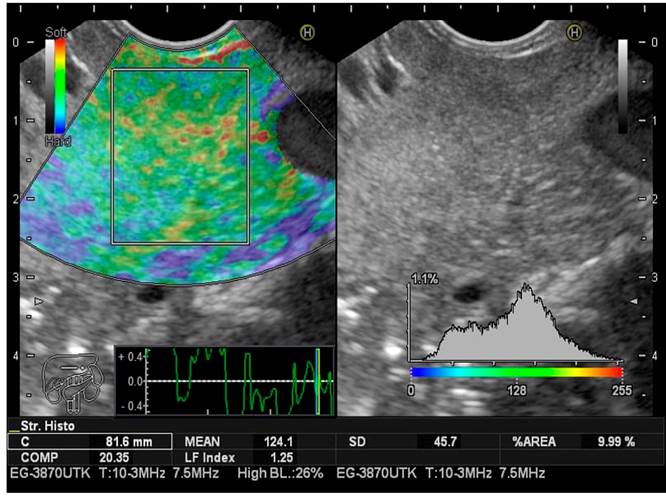

Para limitar el sesgo de selección, durante la ultrasonografía endoscópica se estimó tres veces, en todos los pacientes, el IFH tomado para el páncreas. El valor medio de las tres medidas se consideró el resultado final del análisis. Como ya se describió previamente, el IFH tiene en cuenta 11 parámetros que se utilizan para encontrar patrones de imágenes que evalúen la rigidez del parénquima hepático. Esto se logra con solo ubicar el cursor en el sitio donde queremos medir el IFH, al oprimir el botón “Enter” la computadora calcula inmediatamente este índice. Desde hace aproximadamente una década se usa en ecografía abdominal para la estatificación de la fibrosis hepática, usando imágenes de elastografía (RTE).

El IFH secuencial se logra de la siguiente manera:

Se convierte el área de análisis seleccionado de la imagen RTE en una imagen en escala de colores de 256 cuadros

Se traza el histograma de tensión

Se calcula la media de la tensión relativa (media), la desviación estándar de la tensión relativa (DE), la asimetría del histograma de deformación (SKEW) y la curtosis del histograma de deformación (KURT)

Se binariza la imagen RTE en regiones de blanco y negro: las blancas como de baja tensión (azul) y las negras como todas las demás regiones

Para caracterizar las regiones de baja tensión (azul) se calcula la proporción de regiones de baja tensión dentro del área de análisis seleccionada (% área), y la complejidad de la región de baja tensión (COMP)

Se calcula la entropía (ENT)

Se calcula el momento de diferencia inversa (IDM) y angular del segundo momento (ASM) para evaluar la textura de la imagen RTE

Se realiza un análisis de regresión múltiple para mejorar la precisión del diagnóstico, utilizando todas estas características de imagen, en lugar de diagnosticar con características de imagen individuales, como se muestra en la siguiente ecuación de regresión múltiple23:

IFH = -0,009 x MEAN - 0,005 x SD + 0,023 x % área + 0,025 x COMP + 0,775 x SKEW - 0,281 x KURT + 2,083 x ENT + 3,042 x IDM + 39,979 x ASM - 5,542

Este cálculo se realiza en milisegundos con el software, lo cual no aumenta significativamente el tiempo del procedimiento (Figuras 2,3y4).